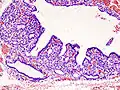

Hyperthyroidism is one of the most common endocrine conditions affecting older domesticated housecats. In the United States, up to 10% of cats over ten years old have hyperthyroidism.[54] The disease has become significantly more common since the first reports of feline hyperthyroidism in the 1970s. The most common cause of hyperthyroidism in cats is the presence of benign tumors called adenomas. 98% of cases are caused by the presence of an adenoma,[55] but the reason these cats develop such tumors continues to be studied.

The most common presenting symptoms are: rapid weight loss, tachycardia (rapid heart rate), vomiting, diarrhea, increased consumption of fluids (polydipsia), increased appetite (polyphagia), and increased urine production (polyuria). Other symptoms include hyperactivity, possible aggression, an unkempt appearance, and large, thick claws. Heart murmurs and a gallop rhythm can develop due to secondary hypertrophic cardiomyopathy. About 70% of afflicted cats also have enlarged thyroid glands (goiter). 10% of cats exhibit "apathetic hyperthyroidism", which is characterized by anorexia and lethargy.[56]